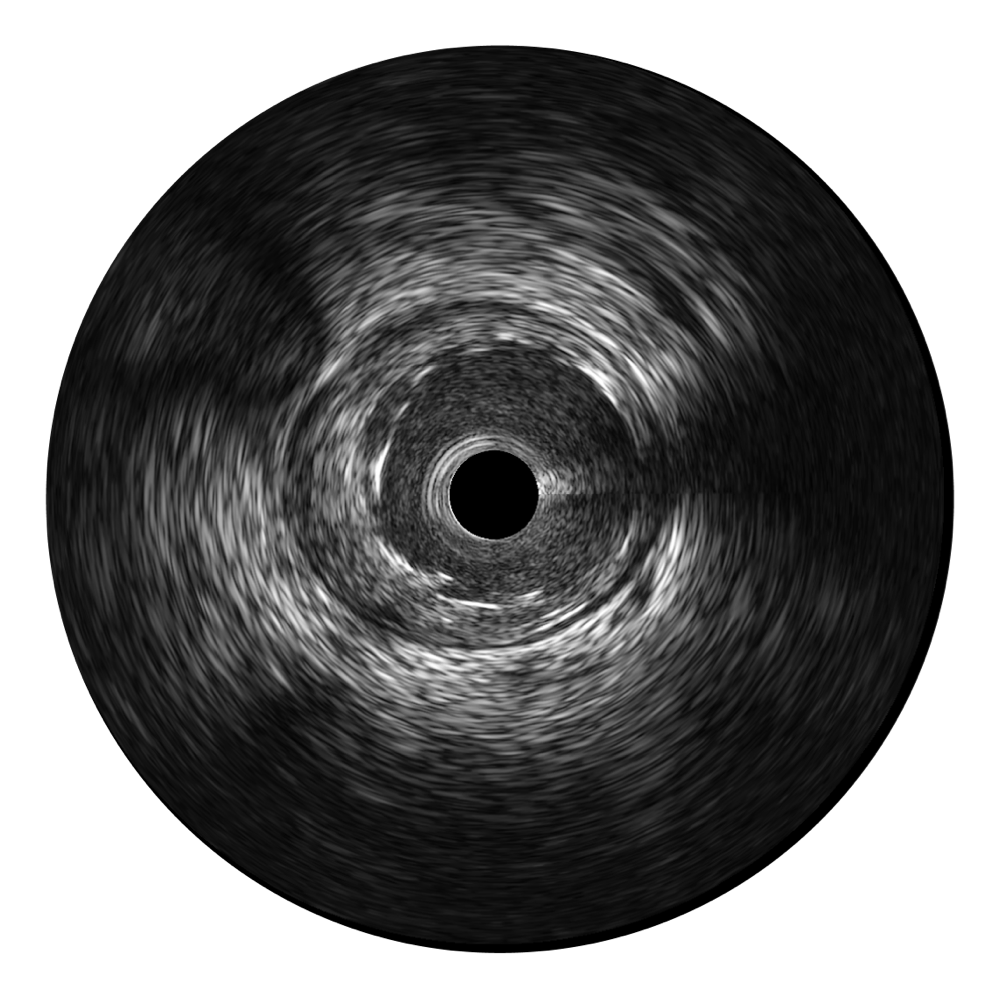

球速体育入口宽频IVUS图像

传统IVUS图像

对比传统IVUS导管成像,球速体育入口宽频IVUS图像的近场支架梁显影更细腻,远场中膜外血管仍清晰可辨,兼顾远中近,兼顾分辨力与穿透深度